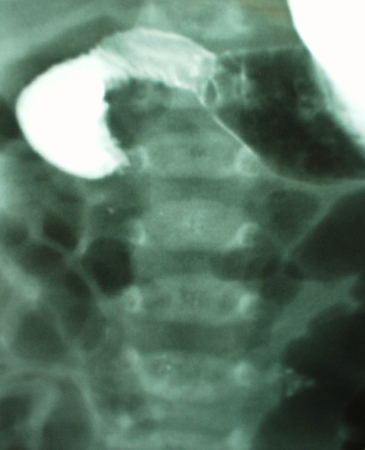

- estudo do trato gastrointestinal superior com contraste:

sinal de bico de pássaro da estenose no local do volvo

Mais - radiografia abdominal:

obstrução parcial ou completa; alças intestinais dilatadas; níveis hidroaéreos; ar livre abdominal com perfuração